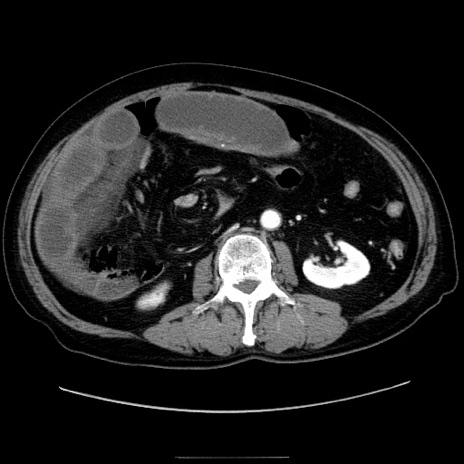

症例30(横断像)

【症例】80歳代男性

【主訴】臍周囲痛

【現病歴】約6時間前から臍下部痛が出現。次第に腹部膨隆・背部痛も生じてきたため来院。背部痛の場所は変化しない。

【身体所見】意識清明、BT 36.3℃、BP  131/87mmHg、P 87bpm、SpO2 100%(RA)、臍周囲自発痛・圧痛あり、反跳痛なし、自発痛部位に一致して板状硬あり、腹部膨隆、腸雑音減弱、CVA tenderness両側陰性。

【データ】WBC 19600、CRP 0.33